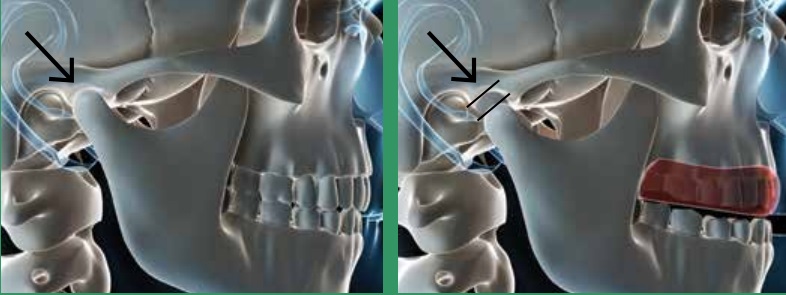

The condylar space is more open and cushioned by the plastic of the mouthguard from impact. It cannot be proven that a well made, well fitting mouthgaurd allows fighters to be able to take more hits, but talking directly to fighters and hearing first hand from their experiences, you would think this is the case.